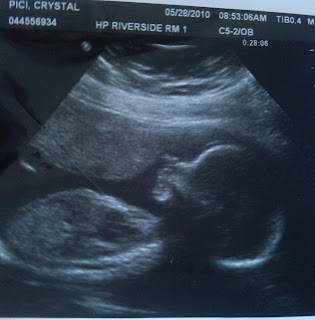

Say hello to baby Pici!! Here are some more pictures with an update at the bottom :) Enjoy!

Update: Our baby weighed at about 13 oz. and measured at around 10.5 inches from head to foot. The anatomy looked great! I'm measuring right on time with my due date which is awesome! We go back at 25 weeks for another check of the heart and get some different angles than we did today. The baby wasn't exactly cooperating as usual ;) He/She started off calm and was hiccuping in the beginning. Then came the stretching, flailing of arms, and tossing and turning! All was calm and perfect when just looking at the baby, however when it came time for measurements, the baby was a handful again! Haha. The tech nearly slipped and said the sex ;) We're going with GIRL! Haha. So keep that pink dust in your thoughts!! I'm down a pound from our 16 week appt which is FANTASTIC!! So far I've stayed in a 3 lb gain range which is great and now I'm down to only 2 so let's keep it up baby!! Hopefully he/she won't be HUGE like Antonio was....10 lbs 8 oz I think?? Heck no!